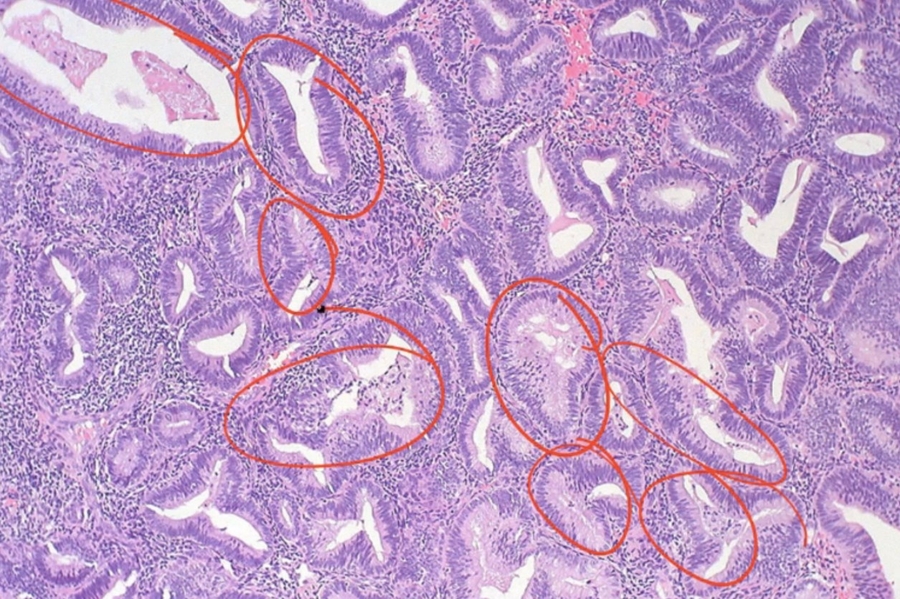

Adenomyosis

_Adenomyosis refers to the presence of endometrial glands and/or stroma within the uterine myometrium.

Adenomyosis will commonly present with menorrhagia, dysmenorrhea. Patients with adenomyosis will have a symmetrically enlarged “boggy” uterus found on bimanual exam. The diagnosis of adenomyosis is made with biopsy, and the definitive treatment is with hysterectomy.

A boggy uterus is a finding upon physical examination where the uterus is more flaccid than would be expected.